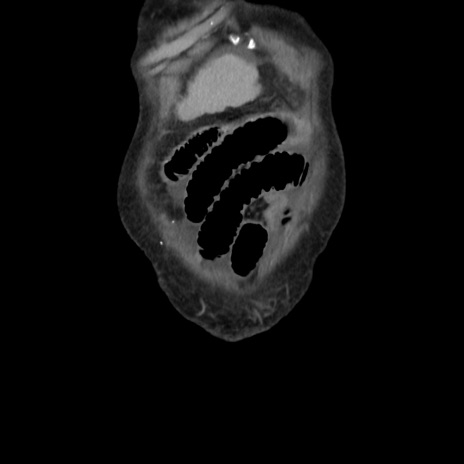

横断像